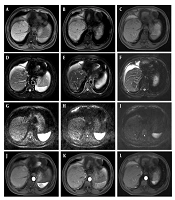

Application of Multimodal Magnetic Resonance Imaging in Postoperative Evaluation of Hepatocellular Carcinoma After TACE Surgery